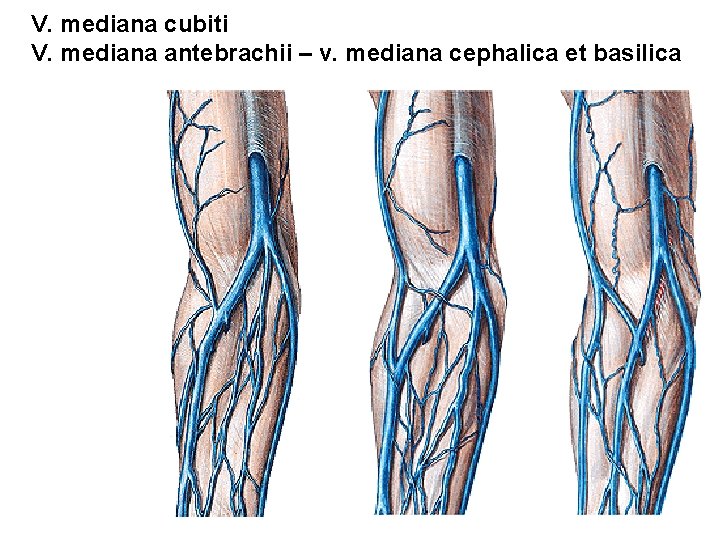

Regio cubiti et antebrachii anterior

V. mediana cubiti V. mediana antebrachii – v. mediana cephalica et basilica